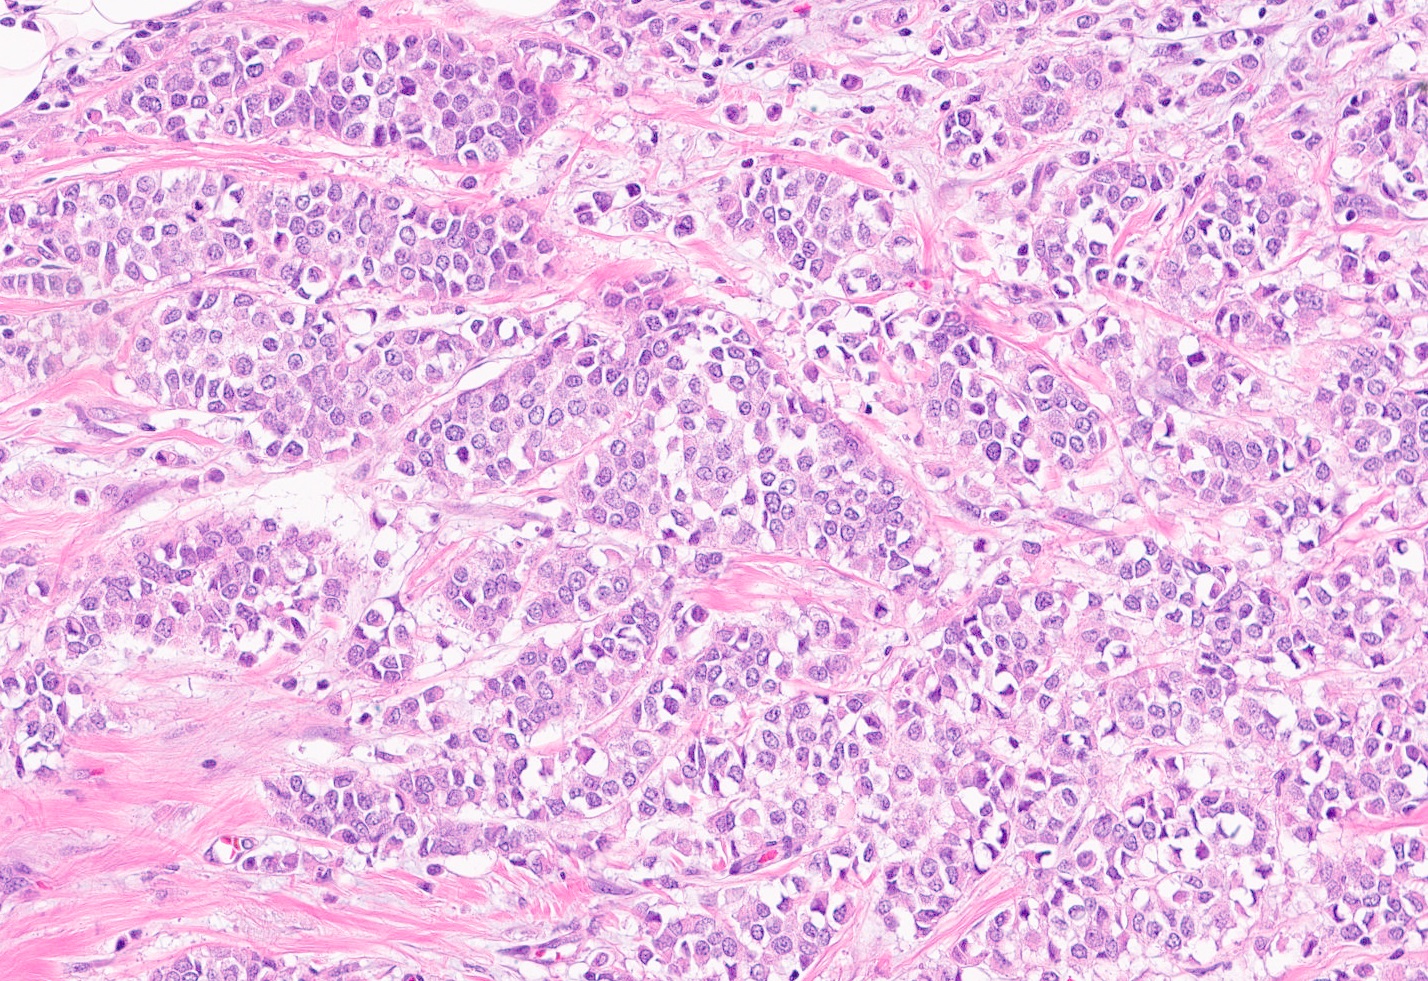

Microscopic (histologic) description

- Tumor cells arranged in single files, cords and single cells (Breast Cancer Res 2015;17:12)

- Can be arranged concentrically around normal ducts, giving a targetoid appearance

- Tumor cells discohesive, small, monomorphic and lacking marked atypia

- Round or notched ovoid nuclei, usually grade 1 or 2 nuclear score

- Scant cytoplasm, occasional with intracytoplasmic lumen

- Mitosis infrequent

- Desmoplastic reaction and necrosis uncommon

Microscopic (histologic) images